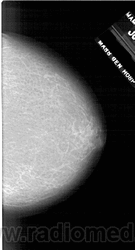

Жирная (не плотная) грудь

Умеренно плотная грудь

Плотная грудь

Маммограммы представляют собой изображения структур, проецируемых на плоскость: плотная грудная маммограмма, следовательно, состоит из многих других структур, которые необходимо проанализировать, чем более жирная, пустая грудь. По этой причине диагностировать рак молочной железы труднее для моложе, чем для пожилых женщин.

Нажмите на миниатюрные картинки, чтобы получить увеличенный размер.